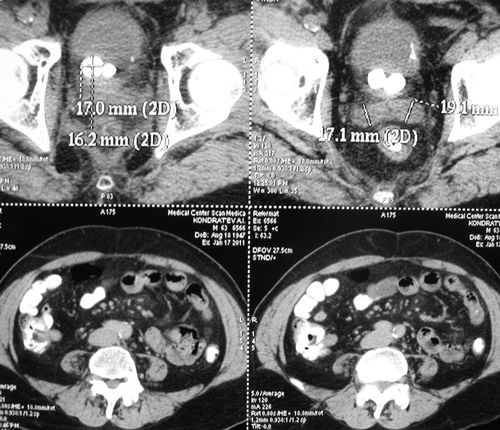

Лучевой цистит с исходом в микроцистис (цистпростатэктомия)